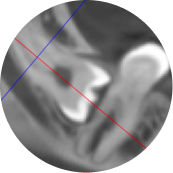

Разрезы и типы лоскутов

Техника остеоэктомии